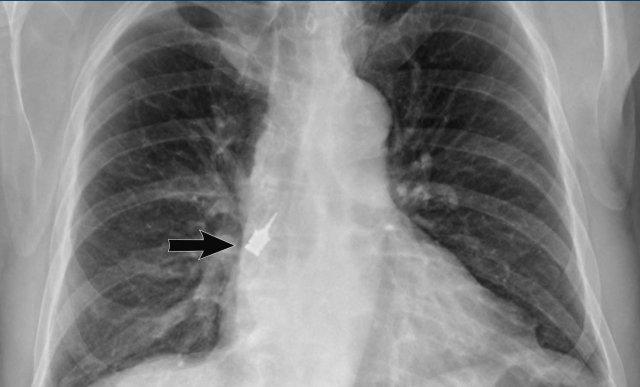

Hình ảnh

Hít sặc dụng cụ trong quá trình phẫu thuật nha khoa, có thể nhìn thấy tại phế quản thùy dưới phải.